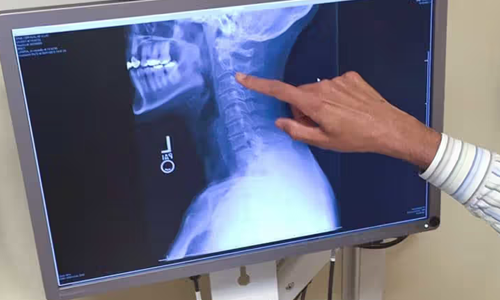

Using a technology that "takes a look" at people's insides and promises early warnings of cancer, cardiac disease, and other abnormalities, clinics and medical imaging facilities nationwide are touting a new service for health-conscious people: "Whole-body CT screening." This typically involves scanning the body from the chin to below the hips with a form of X-ray imaging that produces cross-sectional images.

Digital radiography (DR) is an advanced form of x-ray inspection which produces a digital radiographic image instantly on a computer. This technique uses x-ray sensitive plates to capture data during object examination, which is immediately transferred to a computer without the use of an intermediate cassette.